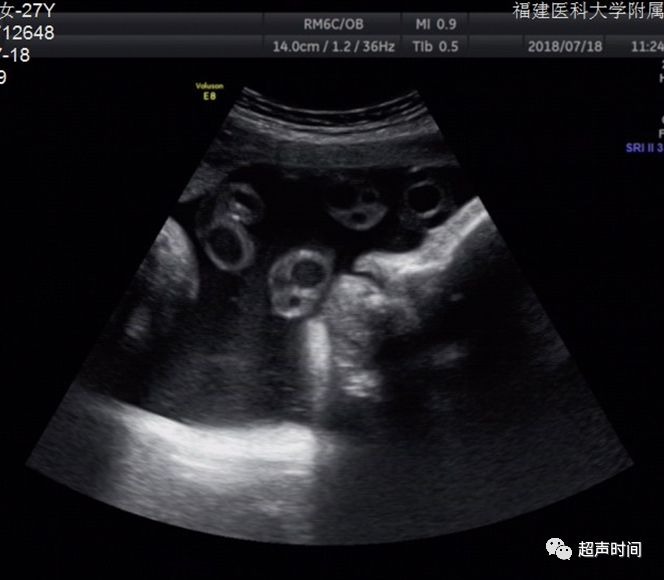

图 5 孕 36 周胎儿面部正中矢状面二维图像,可见舌体增大,伸出口外,且羊水量过多

图 6 孕 36 周胎儿面部冠状面二维图像,显示胎儿舌体增大,充满整个口腔